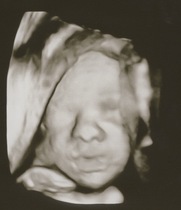

After lots of back and forth, we decided to splurge on a 3D/4D ultrasound as my hospital was offering it for a reasonable price and I felt it would be safe doing it there (felt nervous about a private clinic with this technology for some reason, even though I went to one previously for normal ultrasound).

The experience was equal parts weird and amazing! It was like looking around underwater or on another planet (my uterus) - but seeing the baby move normally, suck his thumbs and rub his eyes was just incredible and reassuring. Some of the pictures came out pretty creepy due to black spots for eyes etc, but a few were cute and we got to see his little face clearly despite my anterior placenta (which baby was cuddling with).

Also, they told us he's measuring 2.5 lbs (1.16 kg) and is in the 73 growth percentile for 27w2d, I hope that doesn't bode poorly for my GD glucose test next week...

@WolfMother326 I wake at different times in the night at least twice, I have to go to the loo every time I wake now and was woken with some big kicks last night. I woke on my back and they kicked me so hard so they were probs saying mum shift it 😂🤣 lovely pics !

@WolfMother326 aw look at those photos! He looks like a cutie already! Your pictures look super clear compared some others I’ve seen. Fingers crossed all clear got GD, 73 just sounds good sized to me 😊